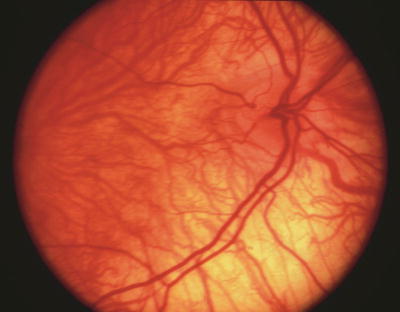

Papillorenal syndrome. The PARSA optic disc is characterized by perturbed angiogenesis, associated renal complications, sans a central retinal artery. Note central excavation with multiple cilioretinal vessels and absence of central retinal vasculature.

Color Doppler imaging has confirmed the absence of central retinal circulation in patients with papillorenal syndrome [286]. Visual acuity is usually 20/20 but may occasionally be severely diminished secondary to choroidal and retinal hypoplasia and, in some cases, to late-onset serous retinal detachments [286]. Peripheral visual field defects corresponding to areas of retinal hypoplasia are often present. The central optic disc excavation and peripheral field defects can simulate coloboma as well as normal-tension glaucoma. Follow-up examination has shown renal disease in some patients who were originally reported as having isolated familial autosomal dominant coloboma [286, 323]. In infants, the bilateral optic disc excavation can simulate congenital glaucoma, but the diagnosis can be established clinically by recognizing the characteristic optic disc morphology [217].

This malformation is attributed to a primary deficiency in angiogenesis involved in vascular development [286]. In these patients, there is a failure of the hyaloid system to convert to normal central retinal vessels. The absence of a well-defined central retinal artery or vein in several adult mammalian species, including lemurs and cats, suggests that this malformation could be considered analogous to an evolutionary regression to a feline pattern of circulation [286]. Because ocular tissues and renal cortex are the most highly perfused tissues of the body, both develop a significant portion of their vasculature by means of angiogenesis (budding) in addition to vasculogenesis [286]. These tissues may thus be particularly susceptible to anomalies in vascular development, resulting in hypoplasia or anomalies of associated structures. Many patients with papillorenal syndrome have no detectable mutations in the PAX2 gene [113, 286].